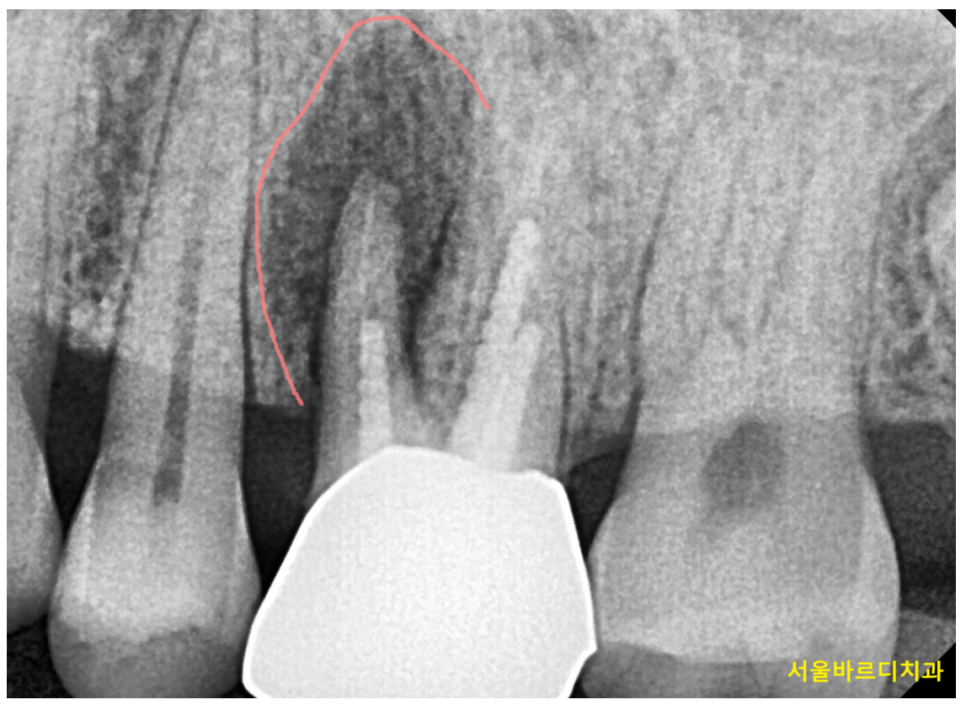

250124 치아 머리 부분에만 문제가 있고 잇몸 부위는 양호한 경우

주로 발치한 부위에 염증이 심하거나

뼈 손실이 있는 경우 이 방식으로 진행합니다.

250214 x-ray 검사로 임플란트 식립 시기 확인할 수 있습니다.

임플란트 식립 시기는 x-ray, ct등을 통해 결정됩니다.

보이지 않는 잇몸 내부안에 잇몸 뼈의 양과 질

염증 유무, 상태 등을 자세하게 관찰 할 수 있는 것이 x-ray입니다.